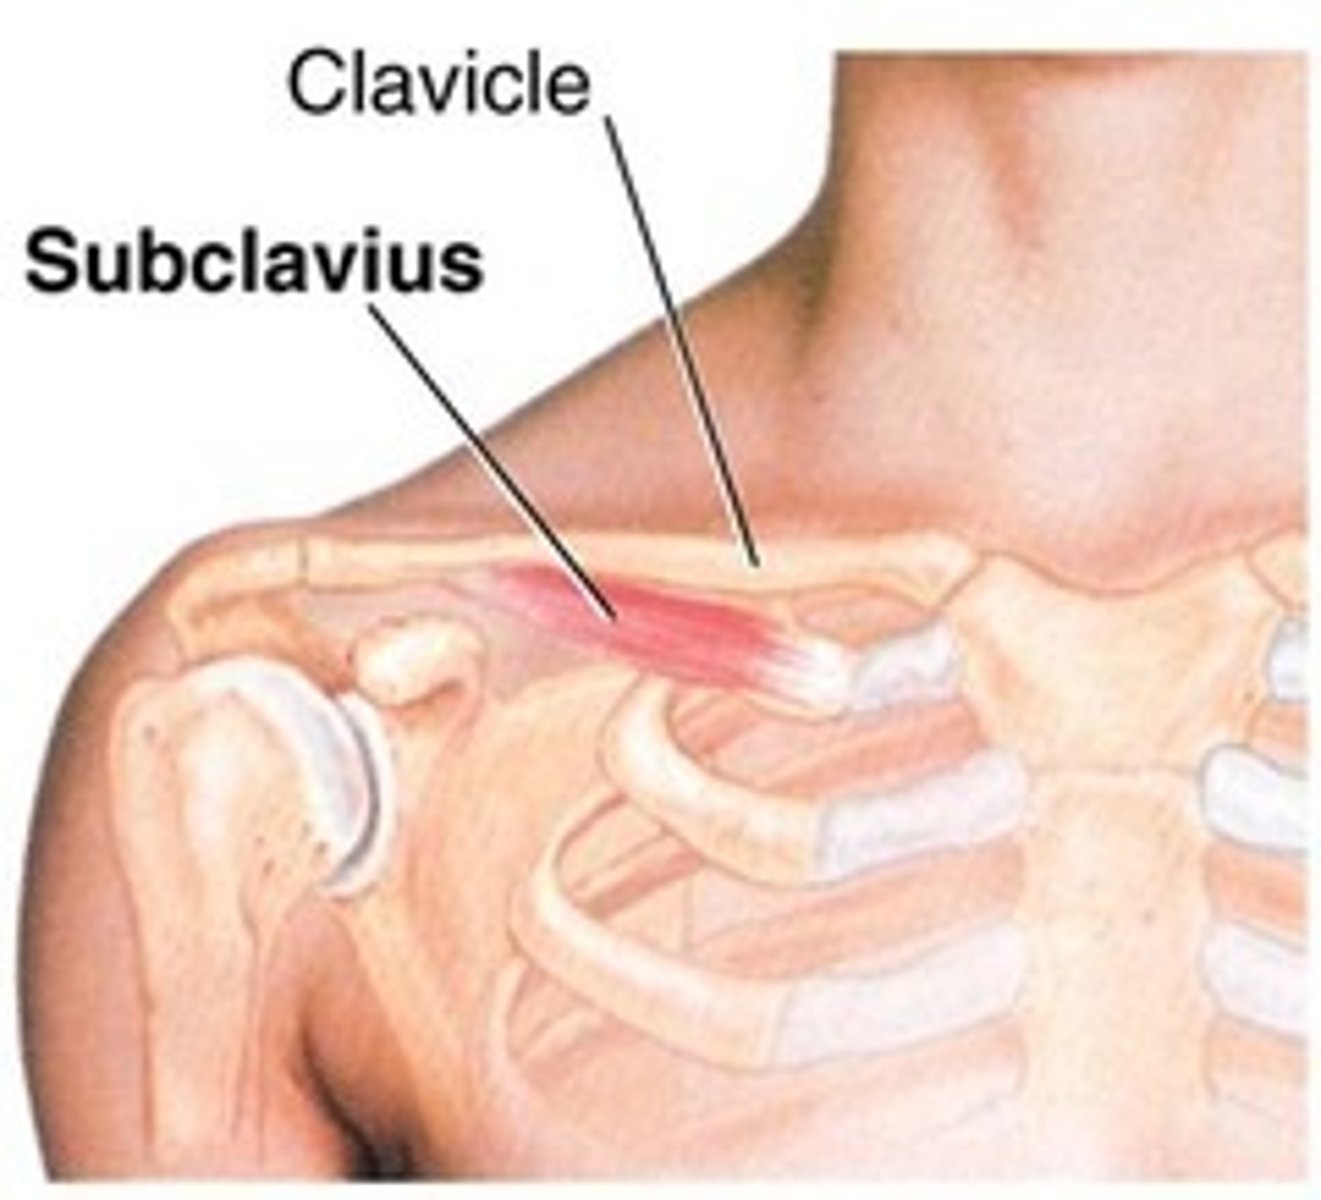

(Anterior axioappendicular muscles:) Subclavius muscle

-Anchors and depresses clavicle

-Nerves to subclavius (C5 - C6)

-Protects subclavian vessels and brachial plexus in case of fracture of the clavicle